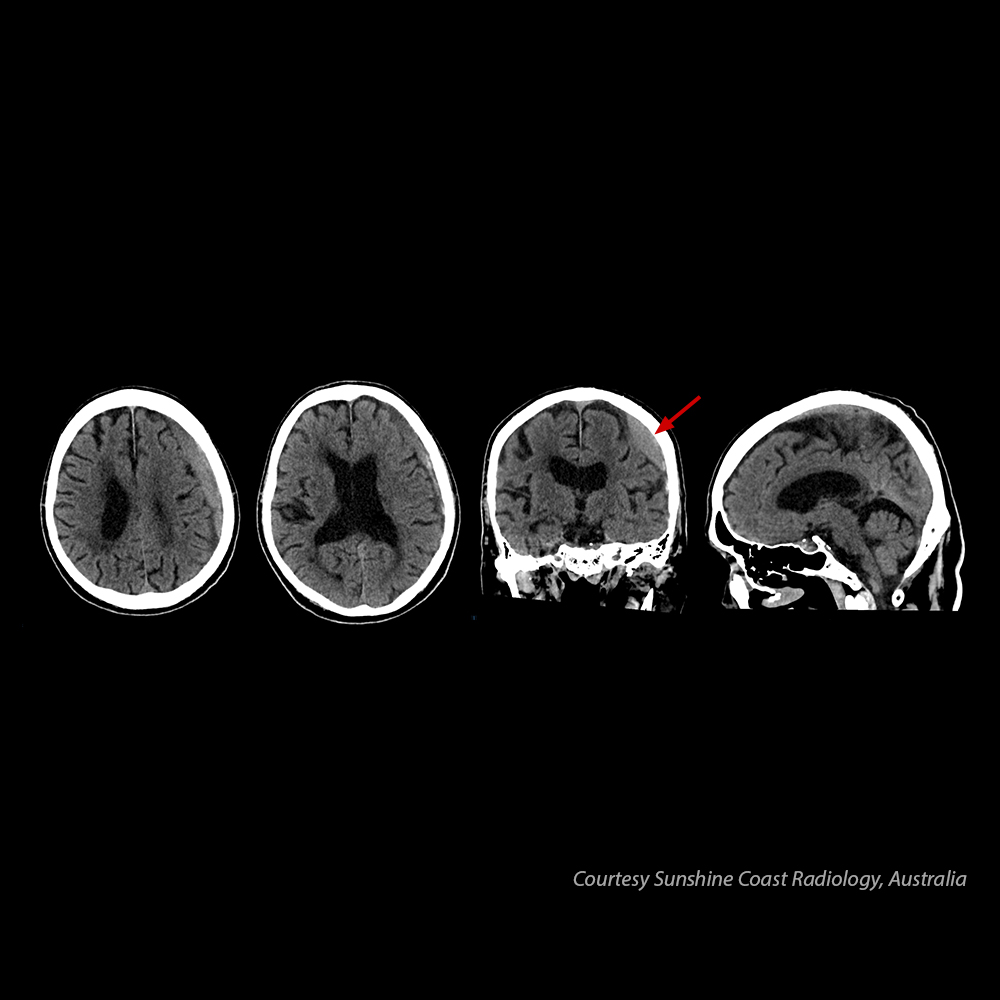

Головний мозок – субдуральна гематома

У пацієнта 80 років спостерігається субдуральна гематома.

Надано Sunshine Coast Radiology, Австралія